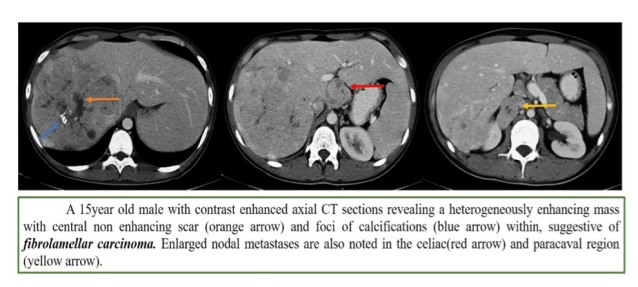

3. Fibrolamellar HCC

- Better prognosis

- Liver lesion looking like spleen on all sequences is bad

- Scar is dark on all sequences (unlike FNH, where it is bright on T2WI)